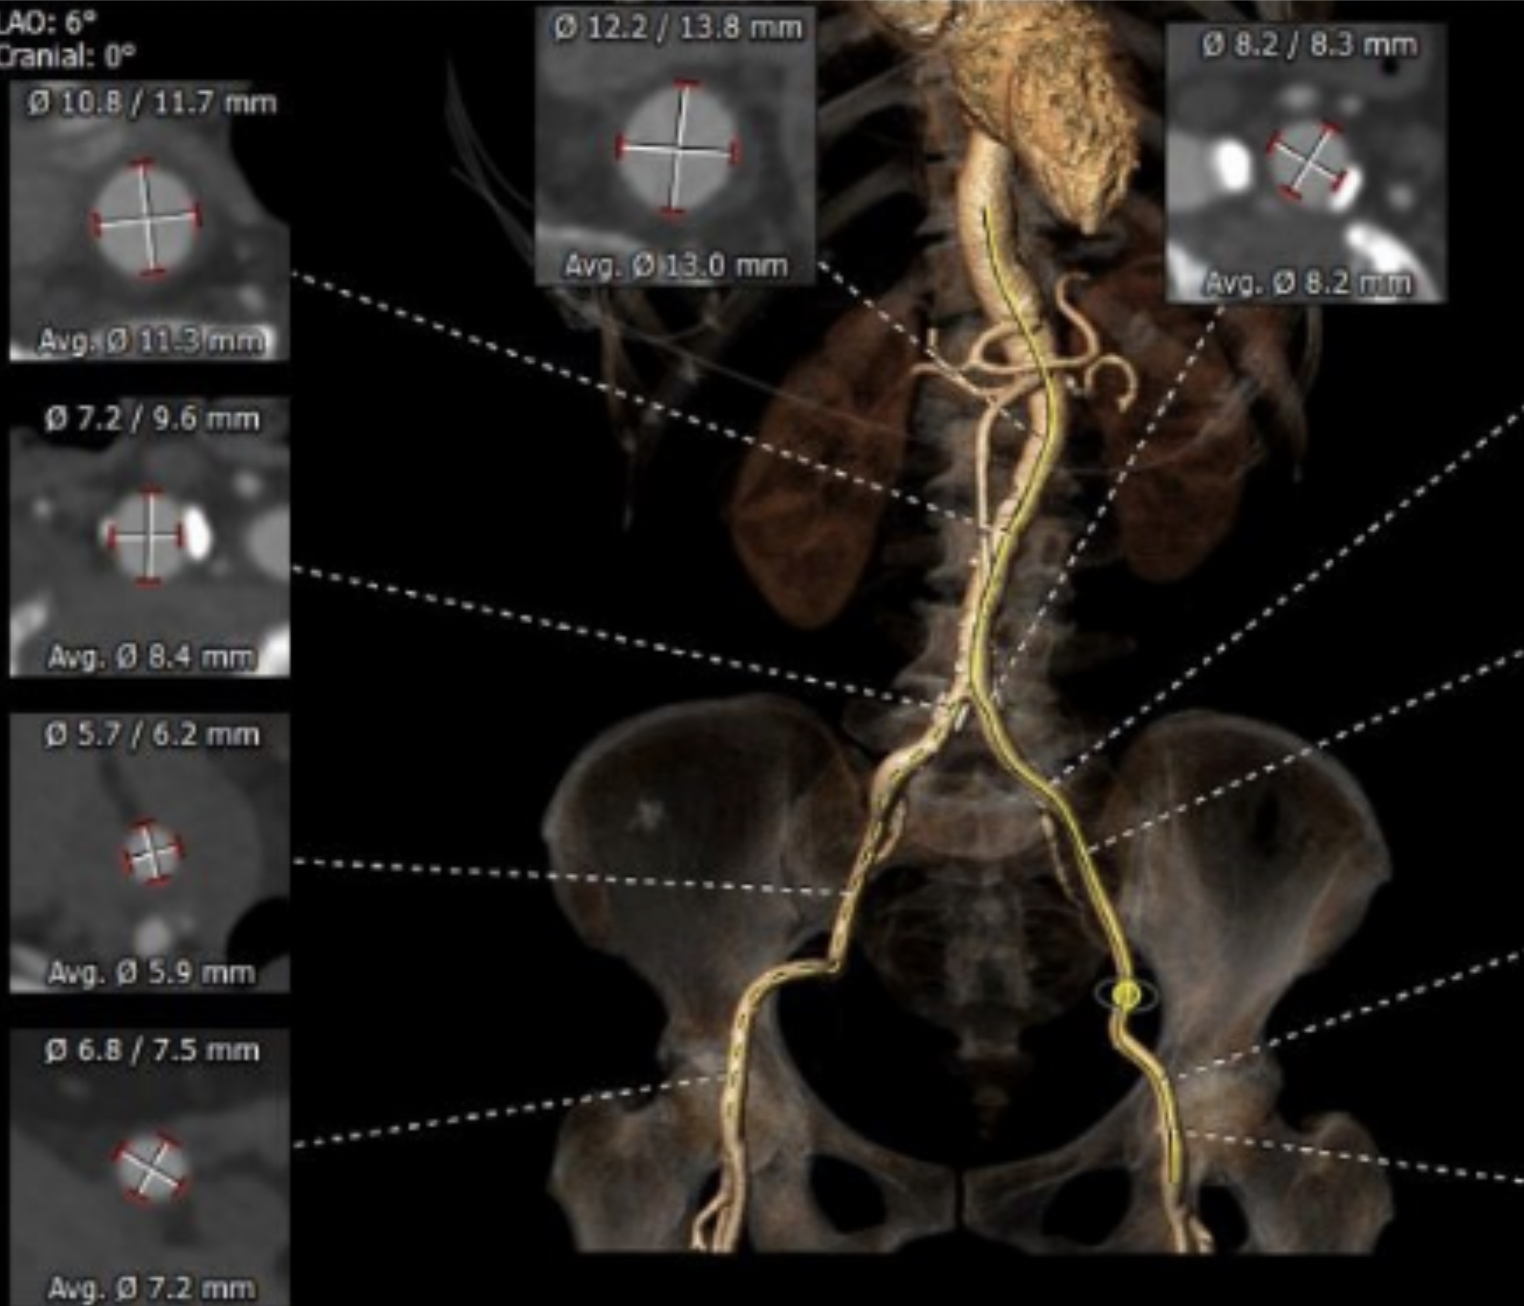

患者71岁老年女性,体重42kg,身高156cm,因突发活动后心累气紧合并心绞痛急诊入院,超声提示主动脉瓣膜重度狭窄,左心功能减低EF 46%,主动脉瓣峰值流速5.2m/s, 平均跨瓣压差68mmHg(图1),冠脉造影提示冠脉未见明显狭窄,患者合并COPD,TIA等并发症,STS评分>6分,经外科团队讨论提示传统外科高风险,经过多学科讨论拟行TAVR手术。术前CTA评价提示三叶式主动脉瓣(图2),Area 479.2mm²,Perimeter 77.9mm,Area折算瓣环直径24.7mm,左侧冠脉开口高度16.1mm,右侧冠脉开口高度16.5mm,瓣膜重度钙化,主要分布于瓣叶,LVOT无特殊,主动脉窦平均内径31mm,患者外周血管尚可无明显钙化扭曲,最细5.9mm(图3)。

图3:外周血管CT提示右侧股动脉入路无明显钙化扭曲,血管较细,最细5.9mm